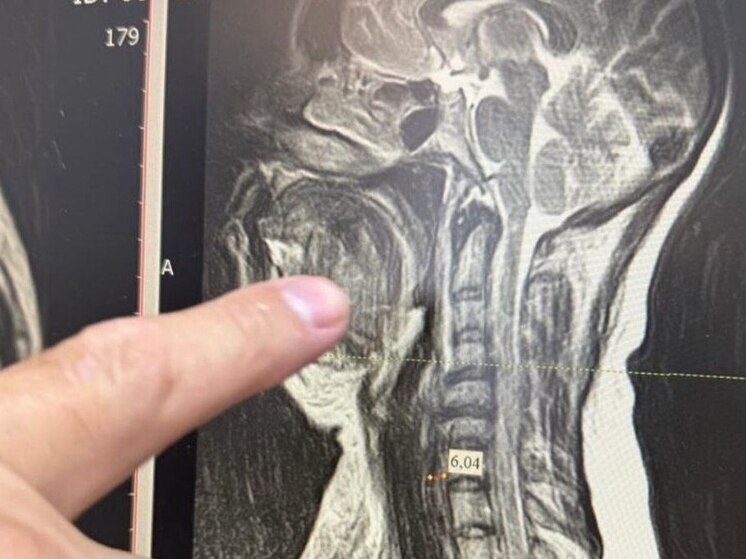

В Ессентуках медики городской клинической больницы провели уникальную операцию по спасению жизни 35-летней пациентки, поступившей в критическом состоянии из-за разрушенного зуба.

Как сообщает пресс-служба городской администрации, у женщины был диагностирован обширный отек шеи, затруднявший дыхание, и высокая температура. Обследование выявило одну из самых опасных форм осложнения — двустороннюю флегмону окологлоточного пространства. Это заболевание без экстренного вмешательства в большинстве случаев приводит к летальному исходу.

Проведение операции было сопряжено с высоким риском. Из-за сильного отека традиционный дыхательный наркоз был невозможен, и анестезиологи обеспечили подачу наркоза через трахею. Челюстно-лицевой хирург Шахбан Мисриев установил пациентке восемь дренажей.